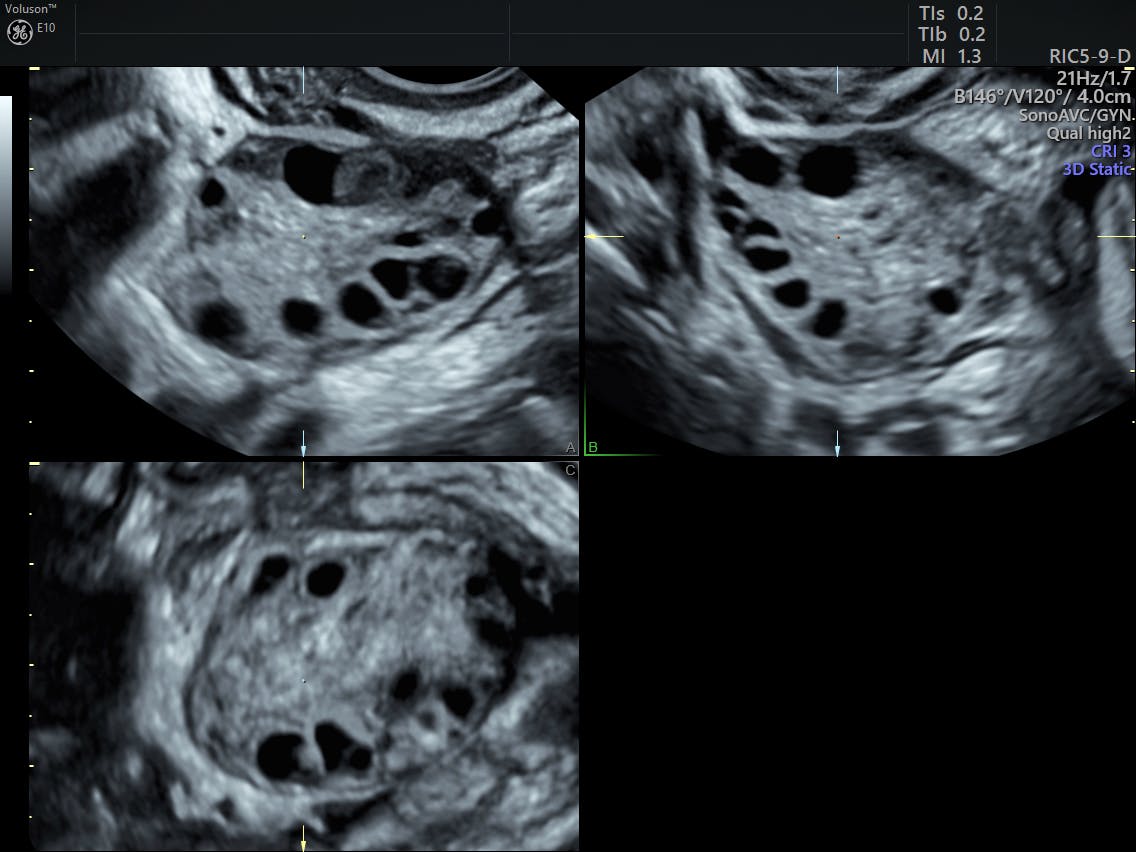

Some women with pcos have cysts on their ovaries. This can lead to problems with your ovaries, such as not having your. When you have pcos, your reproductive hormones are out of balance. Polycystic ovary syndrome (pcos) is the most common endocrine disorder in women of reproductive age that is characterized by reproductive and metabolic disorders. Pcos is a hormonal disorder that affects women. Pcos is one of the most common causes of female infertility, affecting 6% to 12% (as many as 5 million) of us women of reproductive age. Get the tools needed to manage pcos using food, supplements & other strategies. Polycystic ovary syndrome, or pcos, is the most common endocrine disorder in women of reproductive age.

Pcos, polycystic ovary syndrome is a disorder or more likely a hormonal disorder which is common in in this situation of pcos, most women grow numerous small cysts filled with sacs on the ovaries. A lack of ovulation can lead to fertility problems. When you have pcos, your reproductive hormones are out of balance. Management is important in preventing any long term health risks. Here's a checklist of 30 pcos symptoms no woman should ignore. Polycystic ovary syndrome (pcos) is a hormonal disorder common among women of reproductive women with pcos may have infrequent or prolonged menstrual periods or excess male hormone. Polycystic ovary syndrome support groups can help women going through similar experiences. Studies show that women who have a higher bmi pcos is linked to obesity. Pcos treatment depends on the woman's stage of life, which can include medication, birth control pills, and fertility treatments when pregnancy is desired. Information in this subreddit should not be a substitute for obtaining. Pcos isn't the only risk factor for developing diabetes: Polycystic ovary syndrome, or pcos, is the most common endocrine disorder in women of reproductive age. This subreddit is intended to serve as both an educational resource, as well as a safe place to share and listen.